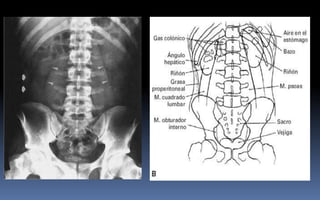

PROYECCION SIMPLE DE ABDOMEN

CRITERIOS DE EVALUACION P.S.A.

 Apreciar desde el abdomen

superior hasta la sínfisis del

pubis.

 Lumbares, pelvis y ultimas

costillas sin rotación.

 Apófisis espinosas en el

centro de cuerpos

vertebrales.

 Ver el bazo, riñones, psoas

y “borde inferior hepático

INTERPRETACION

 Estructuras óseas

(densidades).

 Tejidos blandos.

 Psoas.

 Bazo.

 Niveles Hidroareos.

 Intestino delgado.

 Colon.

 Silueta Renal.

PATRON AEREO DEL INTESTINO